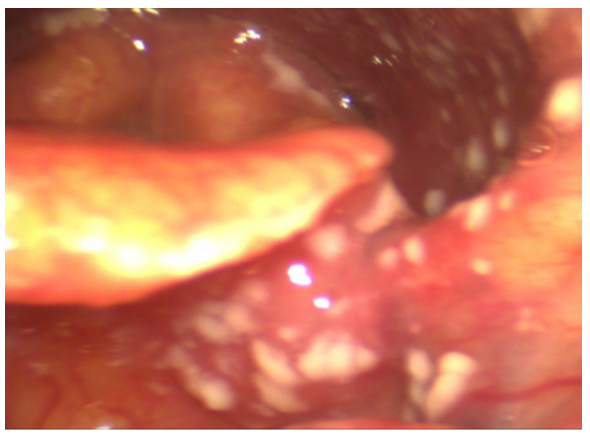

The ENT performed videoendoscopy with 0° rigid and flexible optic fibers. The findings from the videoendoscopy revealed significant abnormalities at the inner third of nasal fossae, pharynx, left tonsillar pillar, left part of soft palate, uvula, (Figure 1) epiglottis (Figure 2) but still sparing glottal and tracheal regions.

Figure 2 Mycosis involving tongue base, left glossoepiglottic vallecula , epiglottis, hypopharynx.